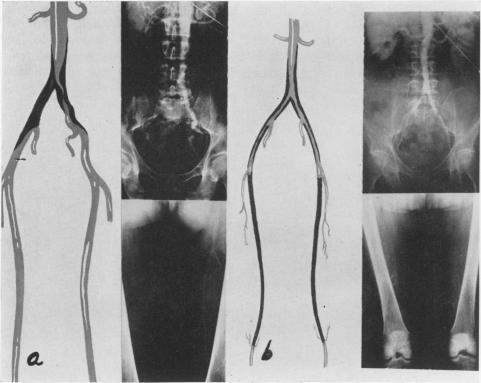

Translumbar Aortography: A Simple, Safe, Technic.

Ann Surg. 1963 Jun;157(6):882-91. doi: 10.1097/00000658-196306000-00006.